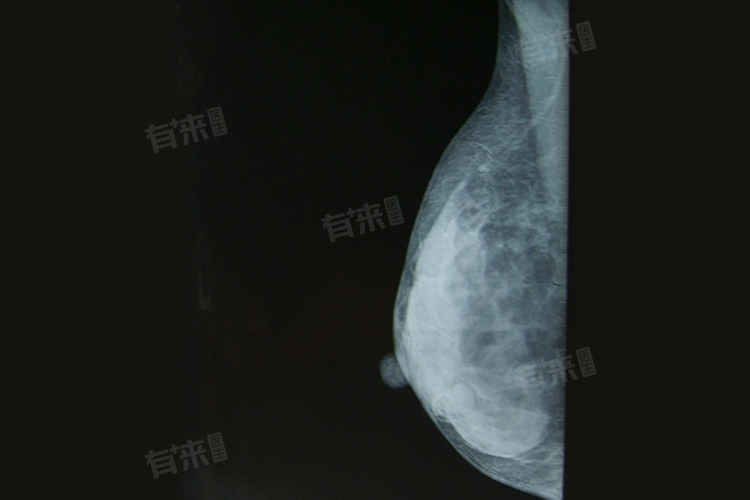

- 乳腺钙化在影像学上具有不同的表现特征,这些特征对判断其性质意义重大。良性钙化通常表现为粗大的、分散的钙化灶,形状规则,如蛋壳样、环状或爆米花样钙化,多位于乳腺的外周区域,且钙化灶之间的距离较大。

- 与之相反,恶性钙化则呈现出微小、密集、不规则的特点,常呈簇状分布,钙化颗粒大小不一,形态可为细沙样、分支状等,多位于乳腺的中央区域或靠近乳头的部位。通过对钙化的这些影像学特征进行分析,结合其他检查结果,能够初步评估乳腺病变的良恶性风险。